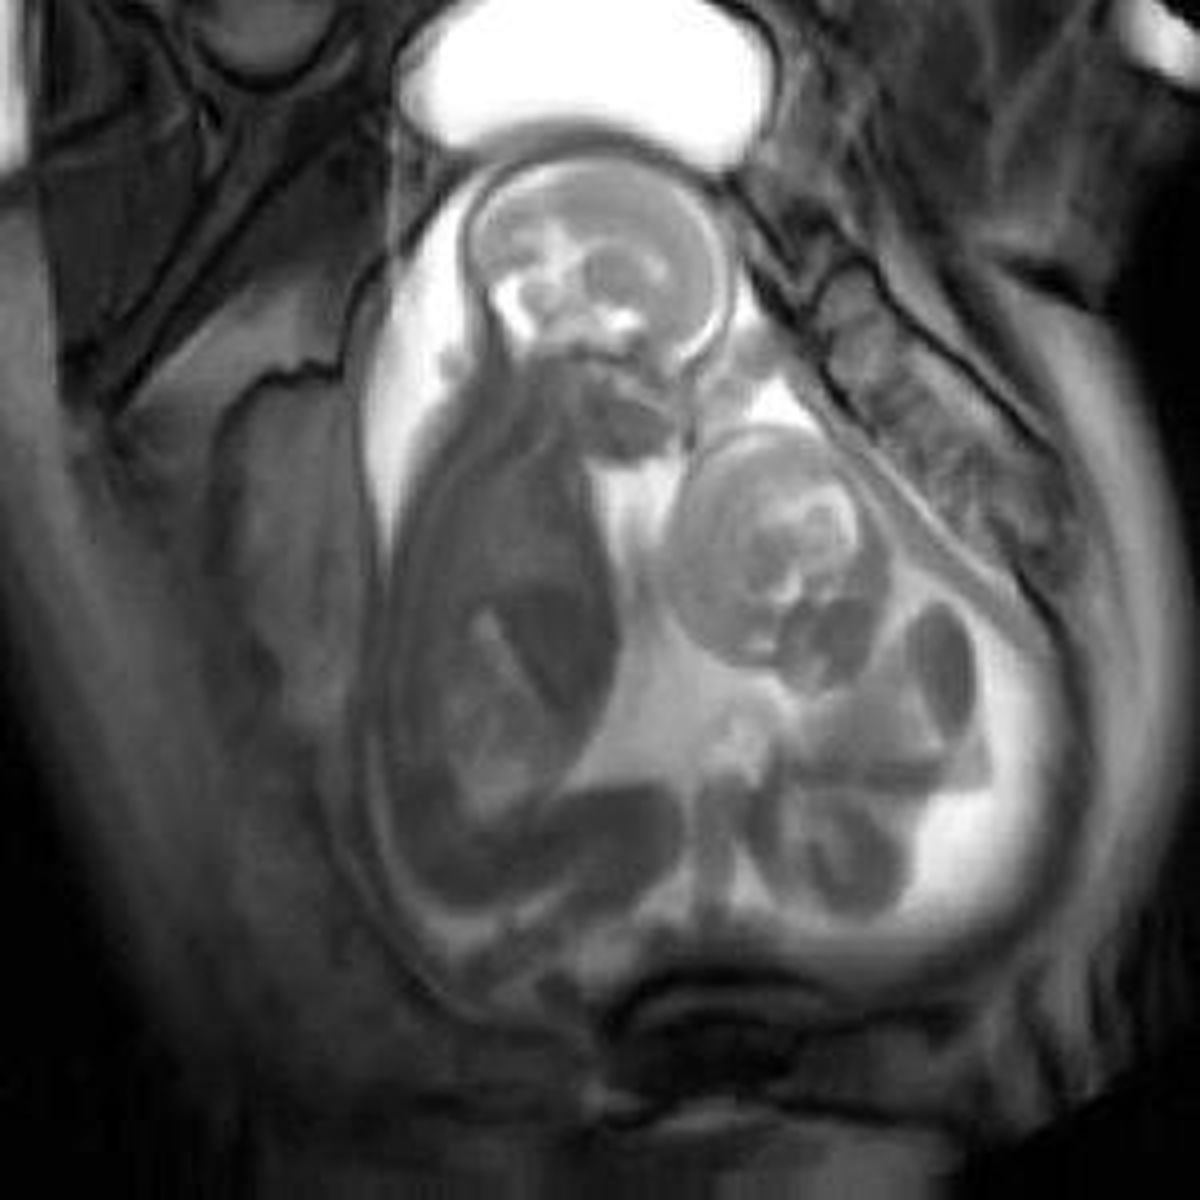

Anne karnındaki bebekler yerleri dar gelince kavgaya tutuştu. O anlar ultrason anında görüntülendi.

İngiltere'nin Londra kentinde bulunan Imperial College'da, MR'a giren hamile kadının karnındaki ikiz bebekler kendilerine daha çok yer açabilmek için dar alanda birbirilerini tekmelerken görüntülendi.

Görüntülerde küçük olan büyüğü tekmelerken büyüğünde ağzının kıpırdaması sanki konuşuyor gibi bir algı oluşturuyor. İlk bakışta komik gibi görünen bu görüntüler aslında çok tehlikeli bir oyunun parçası.